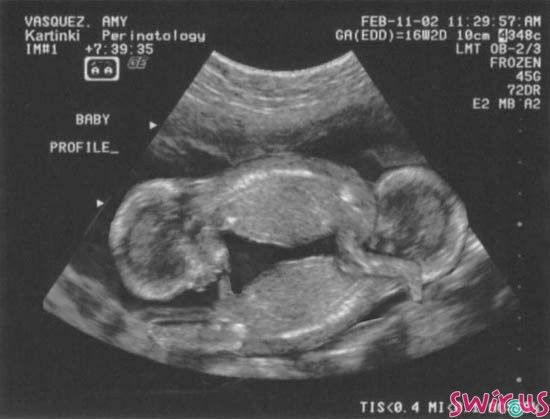

Autor zdjęcia/źródło: http://swir.us/blizniaki

Trafiła do szpitala na łyżeczkowanie. Dobrze, że taki zabieg trwa tylko chwilę, a pobyt w szpitalu również ogranicza się do kilku godzin, bo umarłabym z tęsknoty z moją córeczką. Była jeszcze wtedy takim okruszkiem. Informacja, którą przekazał mi lekarz po zabiegu była okropna. Okazało się, że nosiłam w sobie jeszcze jedno dziecko. Tak, tak... byłam mamą bliźniaków dwu-jajowych. Jeden płód zatrzymał swój rozwój w 3 miesiącu. Miałabym dwójkę maluszków. Moje serce krwawiło, a jednak cieszyłam się, że mam zdrową córkę. Bitwa myśli, w mojej głowie była okropna. Największa radością był moment powrotu do domu i to, że mogłam przytulić Liwię. Byłam niesamowicie obolała i chociaż mama miała mi wtedy pomóc przy córci to chciałam, ją mieć tylko dla siebie. Nie chciałam pomocy, chciałam po prostu czuć, że jest i że jej nie stracę, tak jak moje drugie dziecko.